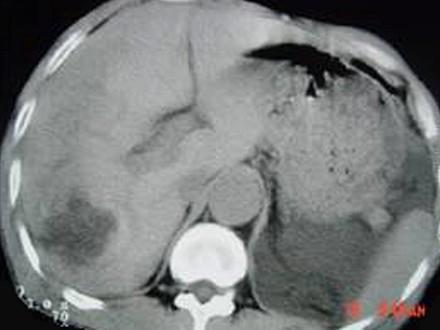

问题 女,62岁,右上腹隐痛,曾在新疆生活30余年,有犬、羊密切接触史,CT平扫如图,最可能的诊断是 ( )

选项 A、肝血管瘤 B、肝包虫病 C、肝癌 D、肝脓肿 E、肝囊肿

答案 B